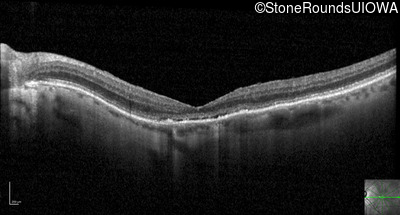

Optical Coherence Tomography - Right - 20/200

Exemplar / OCT Stack

OCT Stack